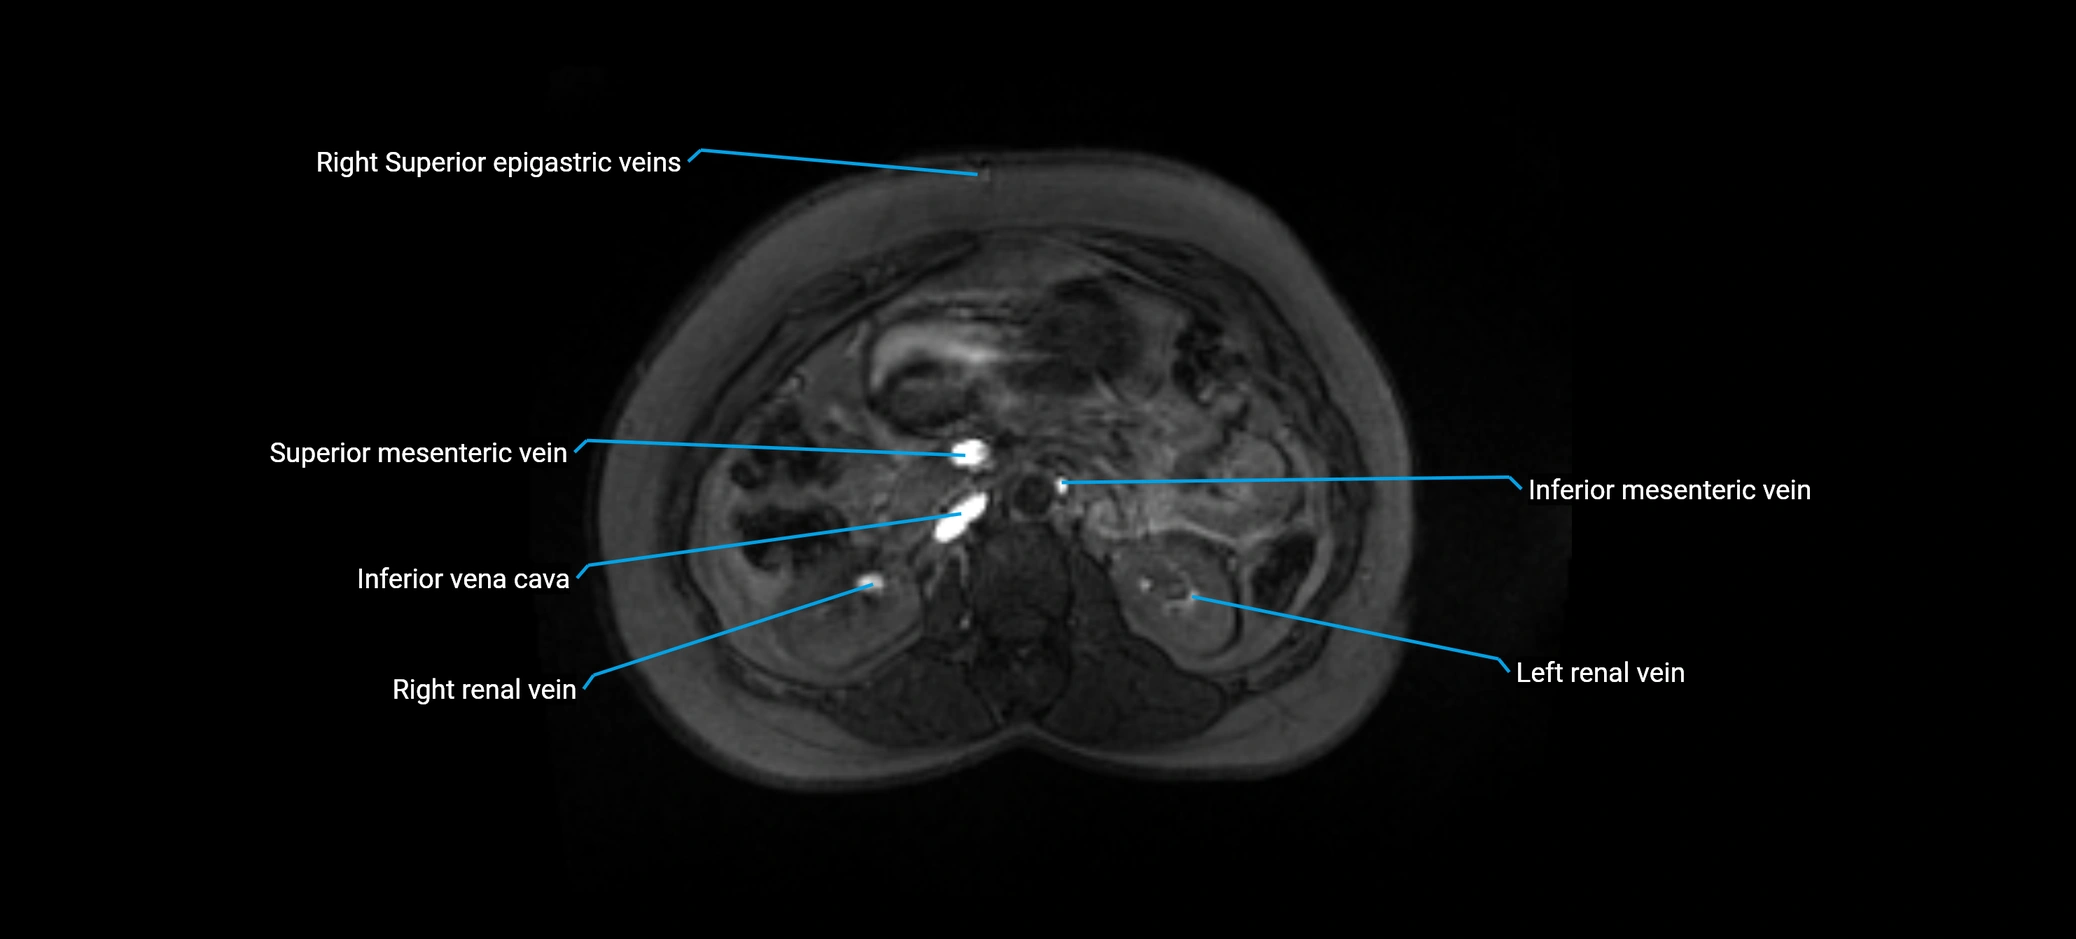

MRI image

image